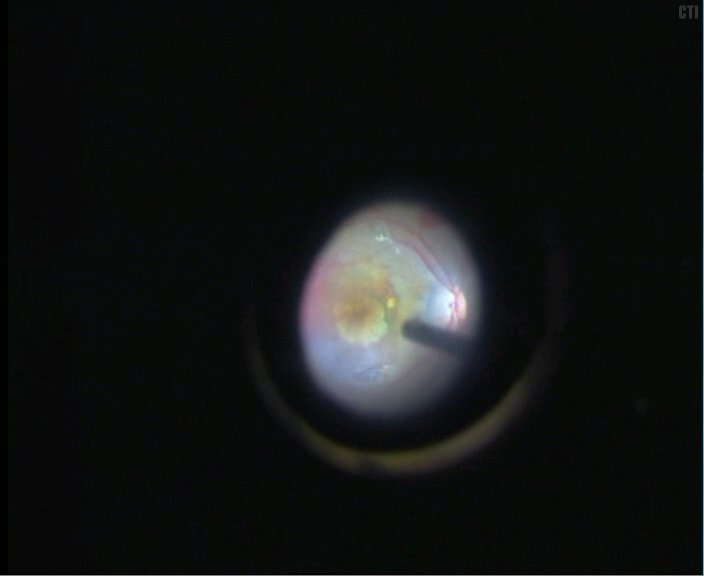

5、视乳头鼻上房取1.5PD大小的色素上皮组织

光凝供体区域-切开视网膜-切开色素上皮及其下的部分脉络膜组织-切断游离出色素上皮植片

6、将色素上皮植片植入黄斑区下

7、手术结束后可见黄斑区下色素上皮移植片